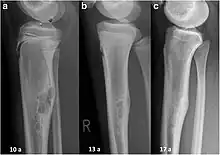

| Non-ossifying fibroma of tibia | |

The most common bone tumor is a non-ossifying fibroma.[4] Average five-year survival in the United States after being diagnosed with bone and joint cancer is 67%.[5] The earliest known bone tumor was an osteosarcoma in a foot bone discovered in South Africa, between 1.6 and 1.8 million years ago.[6]

Primary bone tumors

Primary tumors of bone can be divided into benign tumors and cancers. Common benign bone tumors may be neoplastic, developmental, traumatic, infectious, or inflammatory in etiology. Some benign tumors are not true neoplasms, but rather, represent hamartomas, namely the osteochondroma. The most common locations for many primary tumors, both benign and malignant include the distal femur and proximal tibia (around the knee joint). Examples of benign bone tumors include osteoma, osteoid osteoma, osteochondroma, osteoblastoma, enchondroma, giant cell tumor of bone and aneurysmal bone cyst.